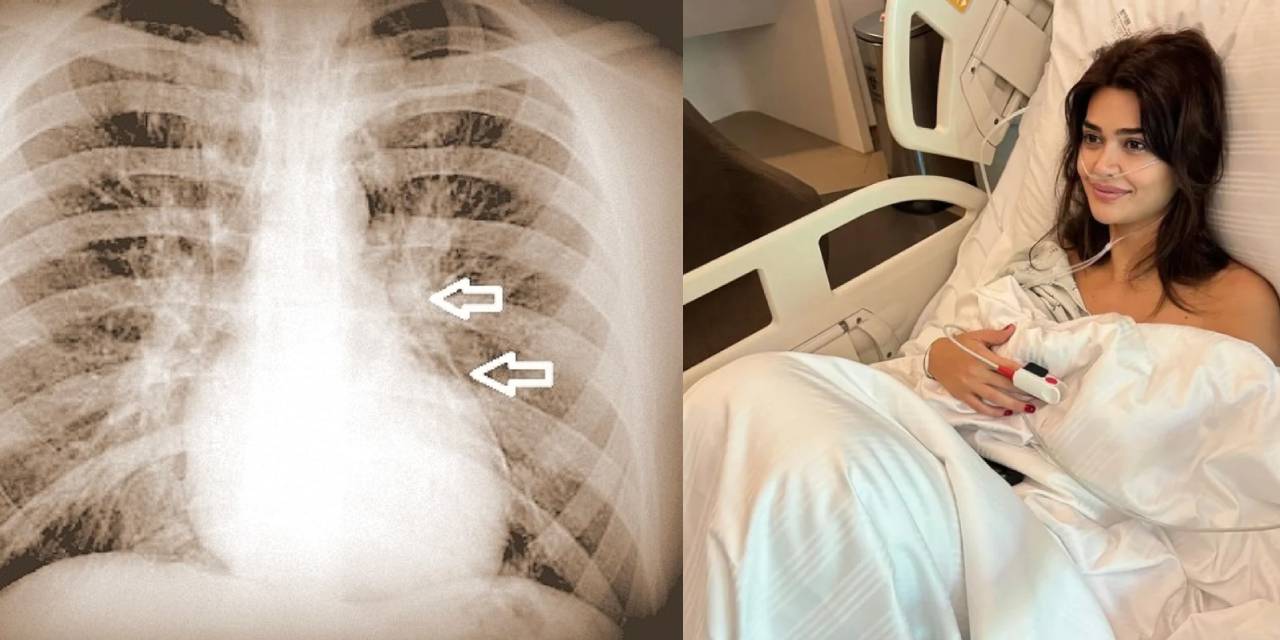

Elektronik sigara oyuncu Selen Görgüzel'in kızını öldürüyordu: Peki Pnömomediastinum nedir? Nasıl belirti verir?